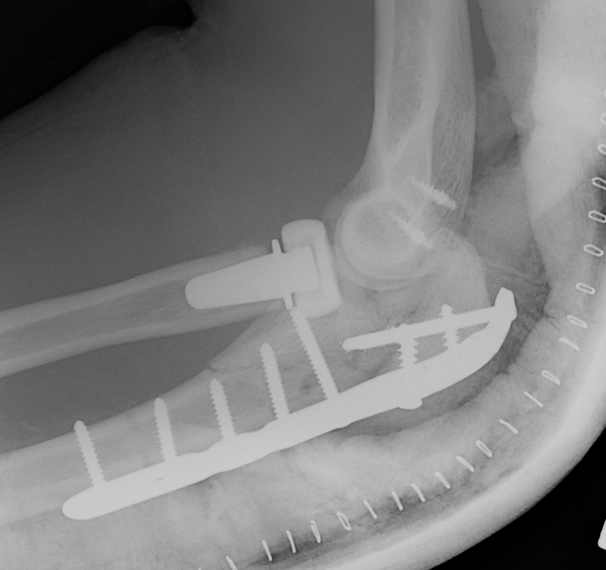

Olecranon plate + ORIF Type II coronoid process + radial head replacement

Olecranon plate with radial head replacement

Olecranon plate with radial head replacement + LCL repair

Olecranon plate + medial coronoid buttress plate + radial head replacement

Complex proximal ulna fracture with radial head replacement subluxation